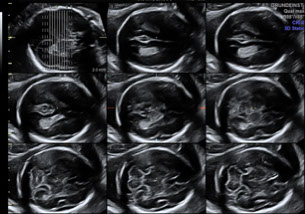

Ultraschall

- Schwangerschaft, inklusive Farbdoppler und 3D Babyfernsehen